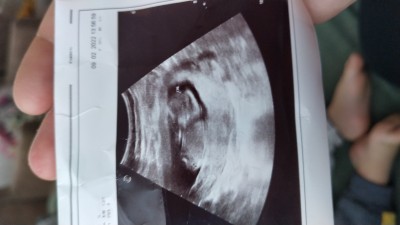

13+4 düz cinsiyet tahmini yapar mısınız lütfen çok meraklıyım

Gebelik haftası 13+4

Ayy bu bebiş kız galiba :)